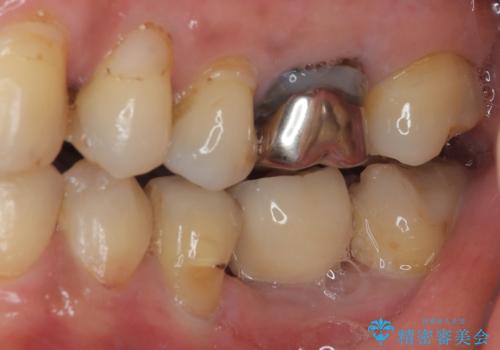

割れてしまった奥歯 1DAYインプラント治療

- 近医にて抜歯が必要と言われていたを何とか残したいとのことで来院された患者様です。

当院では、他院で抜歯と言われてきた歯を何とか保存する治療を多く行ってきましたが、レントゲン上で確認できるほど割れてしまっている歯はさすがに要抜歯と説明をし、インプラント治療を行うこととしました。